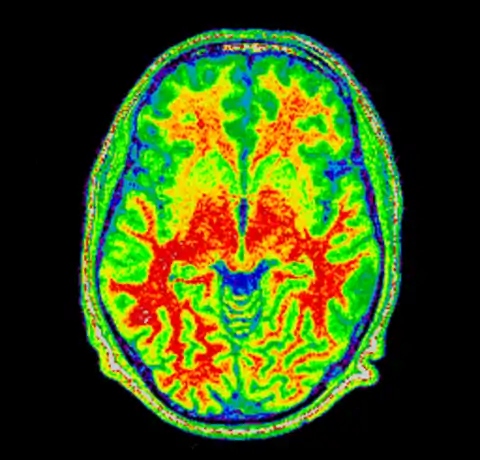

And then for completeness sake, here are the original and corrected image using a spectral colormap to better visualise the change. Note that in the second (corrected) image the intensity of the white matter is more uniform (the red part).